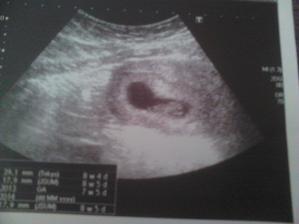

@nonika ano ak vsetko pojde dobre tak ano dakujjem

@lulu19 není zač těším sa stebou aj na ďalšie foto drobcatka